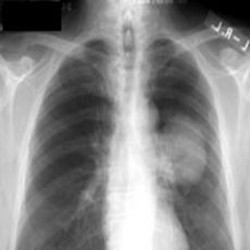

Akciğer hastalıkları belirtileri ve tedavi yöntemleri hakkında bilgiler

Akciğer hastalıkları, kimi zaman evet sırt ağrıları yapabilir Melek'ler. Peki akciğer hastalıklarının belirtileri ve tedavi yöntemleri nelerdir; buyrun öğrenelim.